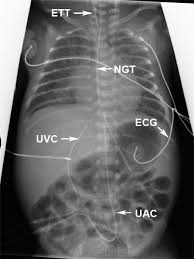

Neonatal Lines Tubes And Catheters Wikiradiography Pediatric Nurse Practitioner Nicu Nurse Pediatric Nursing